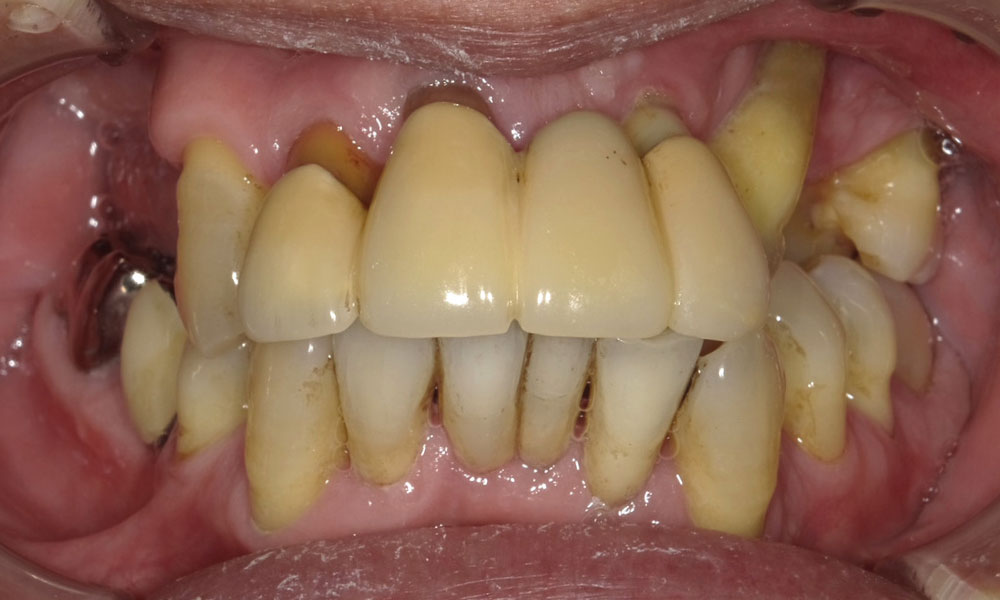

手術前口腔内